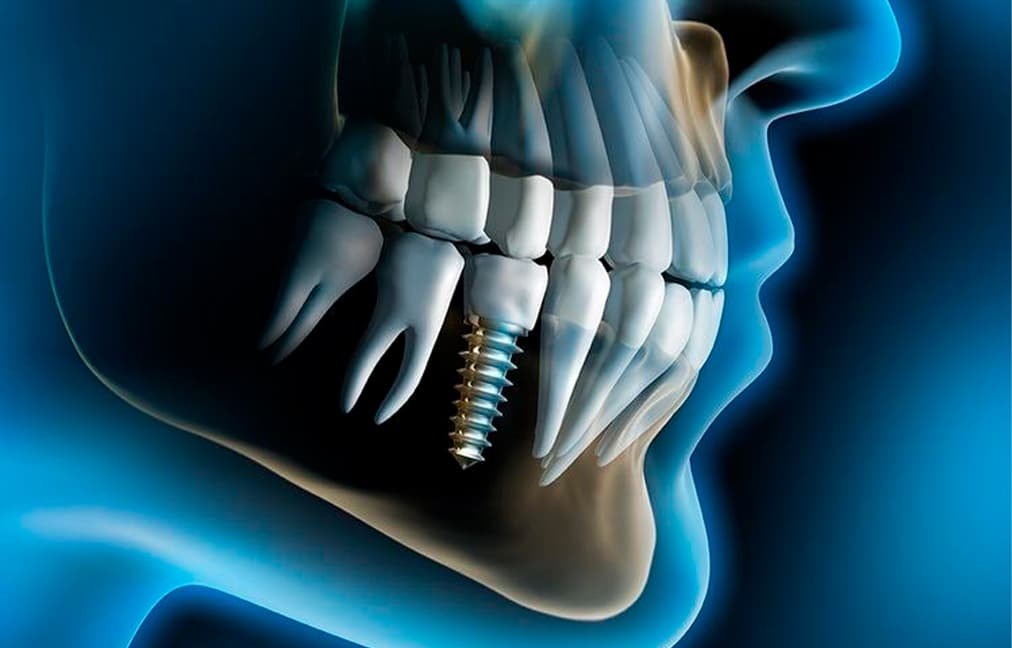

- Комп’ютерна томографія зубів (3D-знімок). На сьогодні це стандарт в стоматології. КТ потрібно, при об’ємному терапевтичному лікуванні, при підготовці до імплантації, протезування, ортодонтії. З його допомогою можна виявити глибокі ураження зубів, кісткові зміни, порушення прикусу.

Рентген зубів необхідний при проведенні терапевтичного лікування (особливо — при лікуванні каналів), протезування, імплантації, а також перед початком ортодонтичного лікування (виправлення прикусу).

- перед імплантацією зубів,

Комп’ютерна томографія (КТ) зубів і щелепи — один з найбільш достовірних і інформативних методів дослідження в сучасній стоматології. Томограф дозволяє зробити знімок в 3D, що дає можливість стоматологам точно і швидко поставити діагноз і запропонувати пацієнтові оптимальне рішення його проблеми.